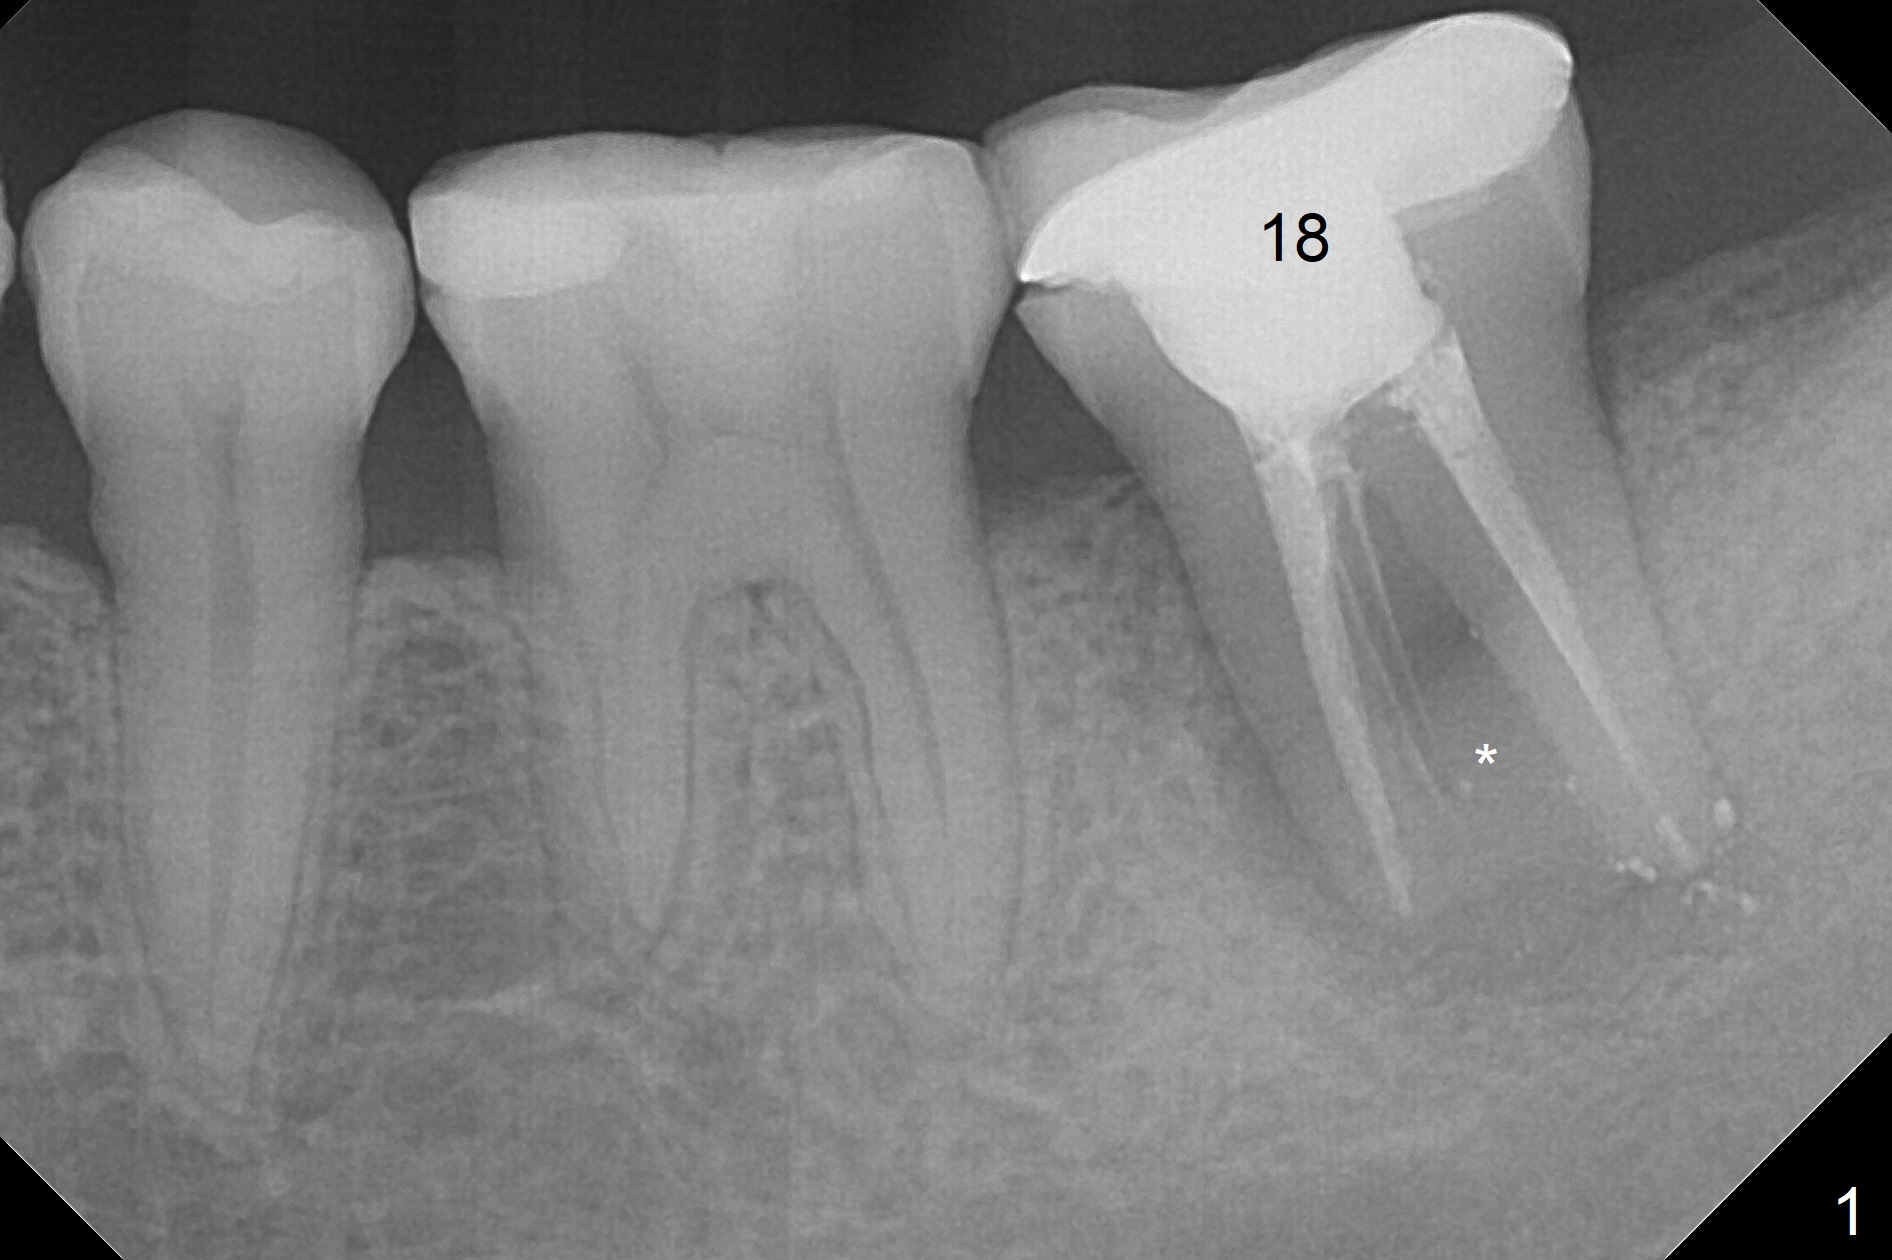

Six months post cementation of #30 implant crown, the 40-year-old woman (CY) returns with chief complaint of lower left abscess. The buccal furca at #18 has inflamed tissue with large radiolucency (Fig.1 *). To avoid the Inferior Alveolar Canal (Fig.2 red dashed line), use taps (most likely starting with 5 mm one) and dummy implants to form osteotomy after extraction and granulation tissue removal. The definitive implant is expected to be 6.5x11 mm. Switch to Tatum implants if the largest IBS is unable to achieve primary stability.